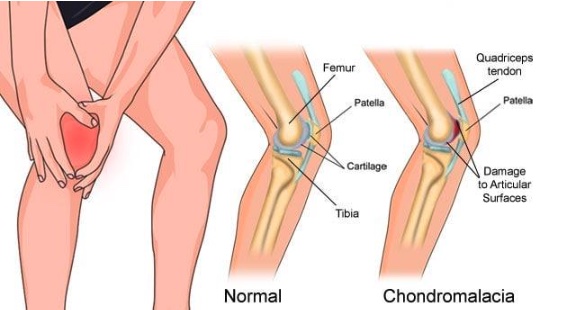

کندرومالاسی کشکک

کندرومالاسی کشکک به معنای نرمی و آسیب غضروف سطح زیرین کشکک (پاتلا) است. این وضعیت معمولاً باعث ایجاد درد جلوی زانو بهویژه هنگام بالا رفتن از پله، نشستن طولانیمدت یا انجام فعالیتهایی با فشار مکرر روی مفصل زانو میشود. این بیماری یکی از دلایل شایع «سندرم درد پاتلوفمورال» محسوب میشود.

علل و عوامل زمینهساز

– ضعف یا عدم تعادل عضلات اطراف زانو

– نارسایی بیومکانیکی در حرکت کشکک

– صاف بودن کف پا یا انحراف زانو (والگوس)

– ضربه مستقیم به زانو یا استفاده بیش از حد

– چاقی یا افزایش وزن ناگهانی

عوارض احتمالی

در صورت عدم درمان، ساییدگی غضروف بیشتر شده و ممکن است به آرتروز زودرس مفصل زانو منجر شود. درد مزمن و محدودیت در فعالیتهای روزمره نیز از پیامدهای دیگر است.